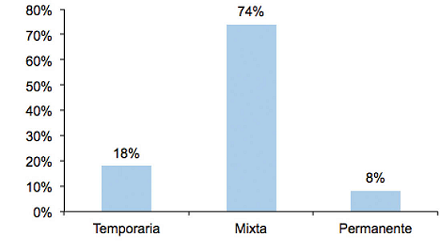

La Figura 3 muestra el porcentaje de sujetos en la muestra según su tipo de dentición.

La Tabla 2 presenta información sobre el tipo de dentición y su asociación con la presencia o ausencia de alguna lesión. La ausencia/presencia de lesiones resulto estadísticamente independiente del tipo de dentición: temporaria (T), mixta (M) y permanente (P) (Chi-cuadrado= 2.8242, valor-p = 0.2436).

Considerando el tipo de dentición del sujeto, se vio que Morsicatio buccarum fue la lesión más frecuente en los tres tipos de dentición (T = 43%, M = 52% y P = 20%), observándose diferencias significativas Chi-cuadrado=6,2136 , valor-p = 0,0447*.